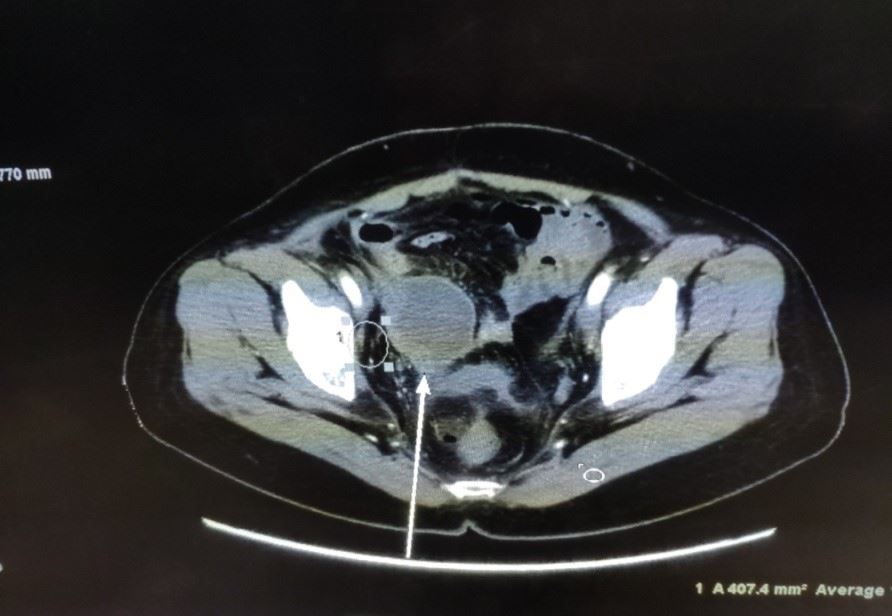

检查后恰逢“五一”假期,她还未收入院,所以只能在家里。我们都担心这个肿瘤有爆裂的风险,她过去的多次转移有3次肿瘤爆裂的情况,这次的肿瘤也很大,如爆裂则有性命之危。在这样极度危险的情况下,她开始每天念九字真言一个小时(一次15分钟,分4次完成),我和另外两个同修每天两次给她远距离发正念,一次10分钟,在此过程中,她的肿瘤部位会有明显的针刺感。这样五天后,五月六日她到院检查,原来无法站立的表姑可以略弯着腰行走了,她自己说疼痛明显减轻了。

更为惊奇的是,医生在做CT增强扫描时发现肿瘤可能出现大面积的坏死(见图2,箭头所指肿瘤的阴影部份),后来对肿瘤进行了穿刺,病理报告证实了,肿瘤中间部份变成了坏死组织和炎症细胞(见图3),而这个肿瘤的表面仍然是肝癌细胞(后补充免疫组化报告)。

'图2'

图2

'图3'

图3

这又是一个天大的奇迹。仅仅五天时间,肝转移瘤居然出现中间大面积坏死现象,肿瘤科主任和PET中心主任均表示肝癌在盆腔的转移瘤在未经治疗的情况下从未见过中间坏死的情况。我想应该是大法的威力让肿瘤坏死。后来表姑做了个射频消融处理了表面的癌细胞,一周后基本恢复正常。